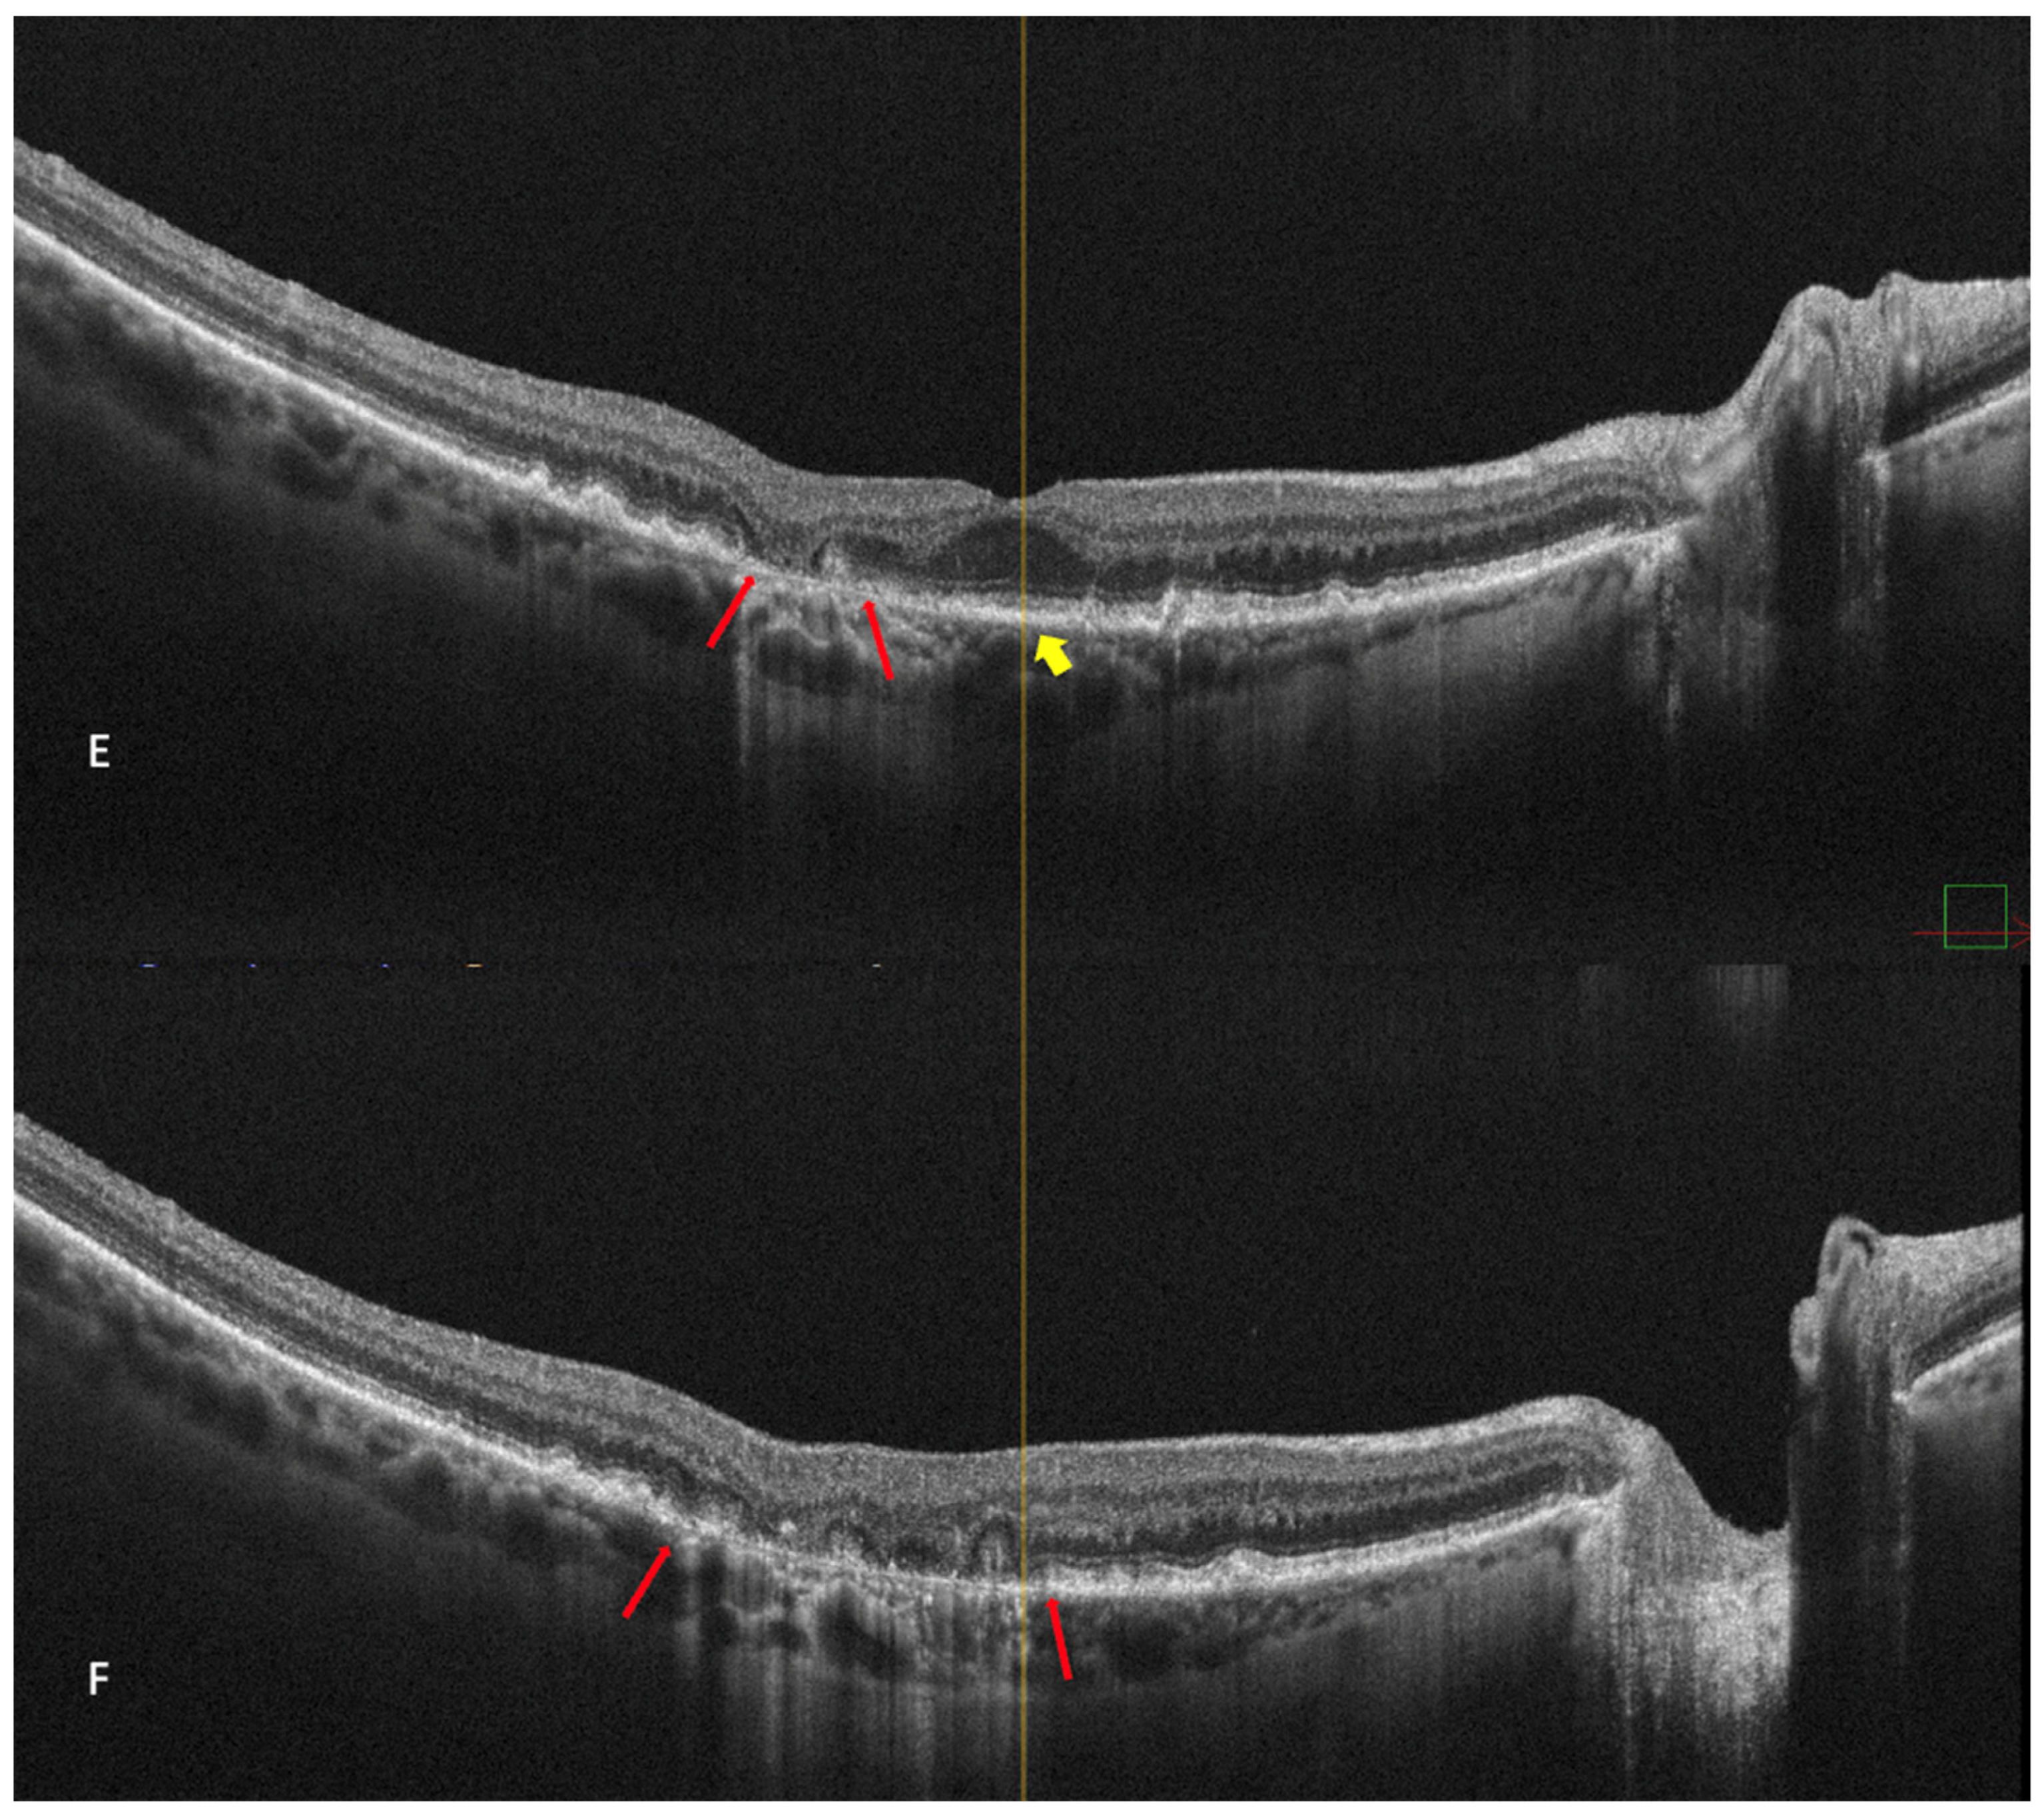

Figure 6.

Geographic atrophy. (A) cSLO image showing round patches of GA where the choroidal vessels are visible, surrounded by large and medium drusen. (B) Green FAF showing confluent hypo-autofluorescent areas. (C) DR and (D) DL retromode images of GA seen as round patches with homogenous reflectivity where the underlying choroidal vessels are visible. (E) SD-OCT showing RPE and outer retinal atrophy temporal to the fovea (red arrows) with foveal sparing (yellow short arrow). (F) SD-OCT showing large area of RPE and outer retinal atrophy (red arrows).

Retromode’s ability to detect and quantify GA was determined by Corradetti et al. by comparison to the classical methods with good and repeatable results [44]. The study compared multiple retinal imaging modalities: retromode deviated-right (DR), retromode deviated-left (DL), confocal color fundus photography (cCPF), and green and blue fundus autofluorescence (G-FAF and B-FAF) using a scanning laser ophthalmoscope [44]. The study revealed the following results using cCFP, G-FAF, B-FAF, retromode DR, and retromode DL, respectively: the mean area of GA was measured as 9.76 mm2, 9.75 mm2, 9.76 mm2, 9.82 mm2, and 9.81 mm2. Even though there was a numeric difference, and the area measured with retromode DR and DL is larger, the difference is not statistically significant and may be due to a greater sensitivity of the method to detect atrophic changes [44].

The aspect of GA on a retromode illumination image is represented by a pseudo3D round patch with a homogeneous reflectivity and clearly visible hyperreflective choroidal vessels seen under the retina (Figure 6C,D) [44].